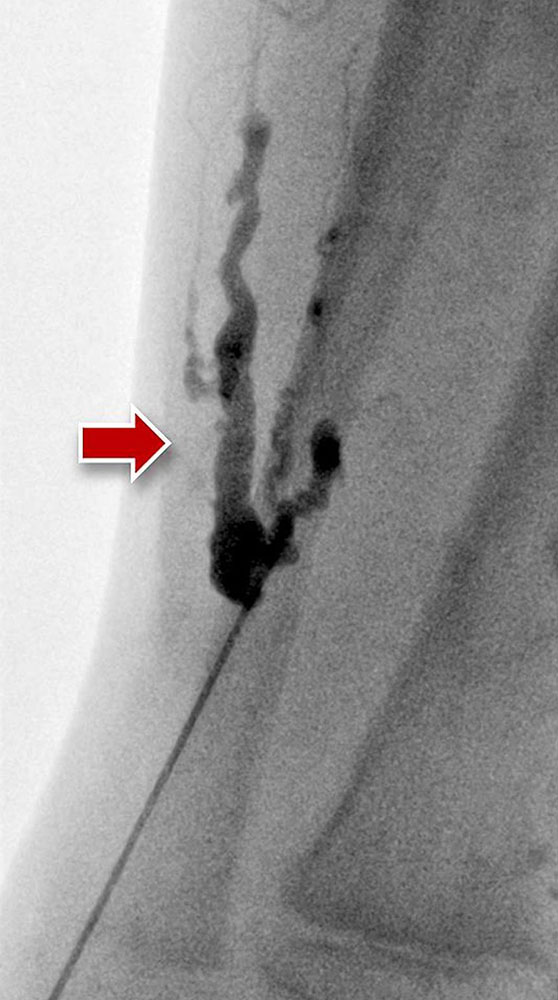

Today, diagnostic phlebography has lost much of its diagnostic significance because of the high informative value of an MRI. However, the direct contrast imaging of venous structures by direct injection is an integral part of sclerotherapy of venous malformations. The vascular malformation is usually punctured directly under ultrasound guidance and visualized with an X-ray contrast medium.

Venous malformations are typically tubular or lobulated, sponge-like dysplastic vascular spaces, which are almost always connected to very small or larger draining veins (communicating veins). Contrast filling defects within the venous malformation correspond to intraluminal thrombi or phleboliths. Direct puncture of the lesion with a needle and subsequent injection of contrast medium aims to identify larger veins of the malformation communicating with the deep venous system immediately prior to sclerotherapy. Any larger communicating veins should be closed. In addition, the contrast injection confirms the needle position and provides an estimate of the size and volume of the punctured part of the venous malformation.